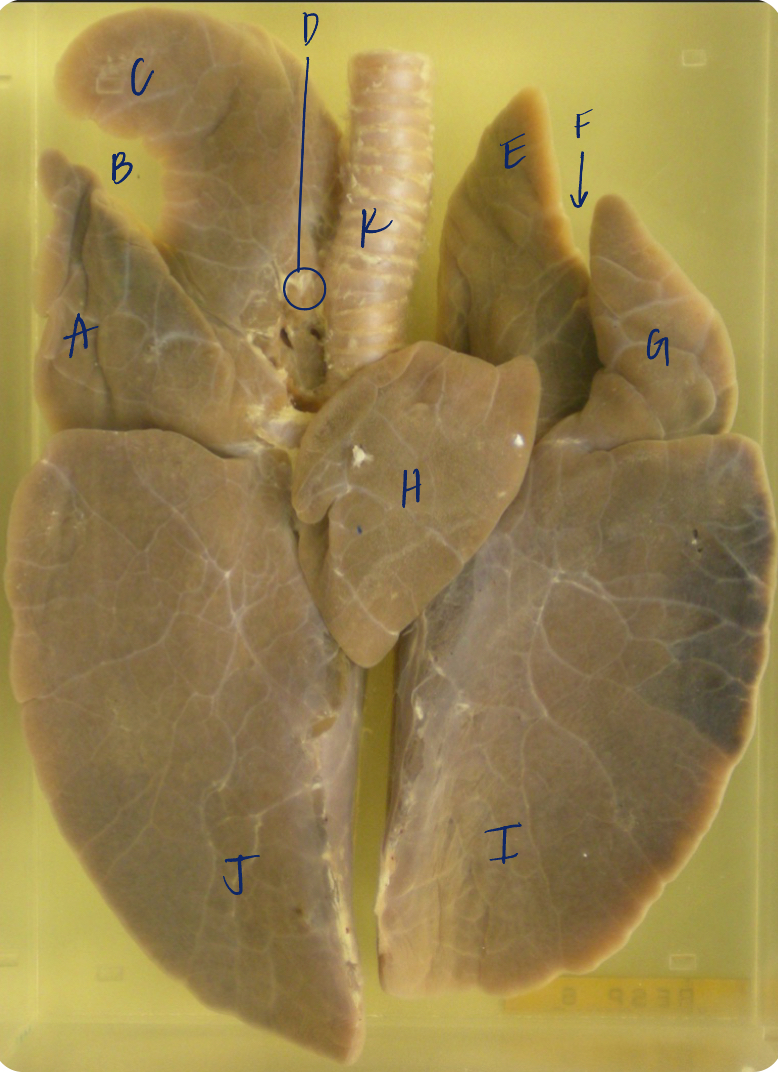

A

(pig lungs, ventral)

middle lobe

B

(pig lungs, ventral)

cardiac notch

C

(pig lungs, ventral)

R cranial lobe

D

(pig lungs, ventral)

tracheal bronchus

E

(pig lungs, ventral)

L cranial lobe, cranial segment

F

(pig lungs, ventral)

cardiac notch

K

(pig lungs, ventral)

trachea

G

(pig lungs, ventral)

L cranial lobe, cranial segment

H

(pig lungs, ventral)

accessory lobe

I

(pig lungs, ventral)

L caudal lobe

J

(pig lungs, ventral)

R caudal lobe